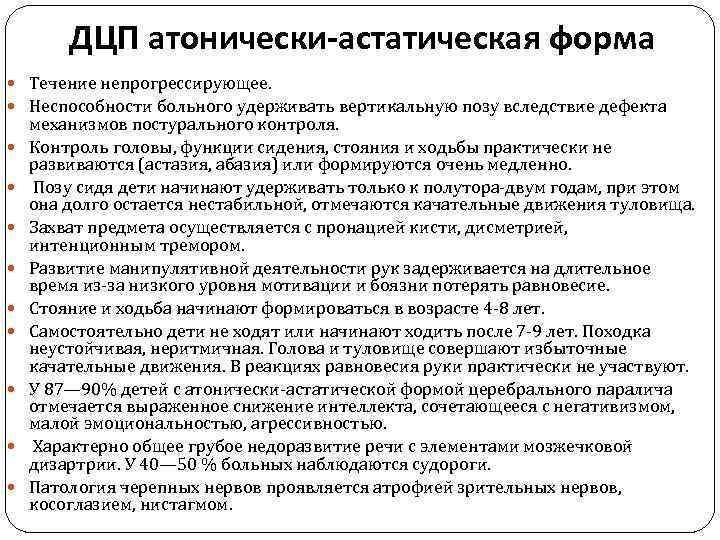

ДЦП атонически-астатическая форма Течение непрогрессирующее. Неспособности больного удерживать вертикальную позу вследствие дефекта механизмов постурального контроля. Контроль головы, функции сидения, стояния и ходьбы практически не развиваются (астазия, абазия) или формируются очень медленно. Позу сидя дети начинают удерживать только к полутора-двум годам, при этом она долго остается нестабильной, отмечаются качательные движения туловища. Захват предмета осуществляется с пронацией кисти, дисметрией, интенционным тремором. Развитие манипулятивной деятельности рук задерживается на длительное время из-за низкого уровня мотивации и боязни потерять равновесие. Стояние и ходьба начинают формироваться в возрасте 4 -8 лет. Самостоятельно дети не ходят или начинают ходить после 7 -9 лет. Походка неустойчивая, неритмичная. Голова и туловище совершают избыточные качательные движения. В реакциях равновесия руки практически не участвуют. У 87— 90% детей с атонически-астатической формой церебрального паралича отмечается выраженное снижение интеллекта, сочетающееся с негативизмом, малой эмоциональностью, агрессивностью. Характерно общее грубое недоразвитие речи с элементами мозжечковой дизартрии. У 40— 50 % больных наблюдаются судороги. Патология черепных нервов проявляется атрофией зрительных нервов, косоглазием, нистагмом.